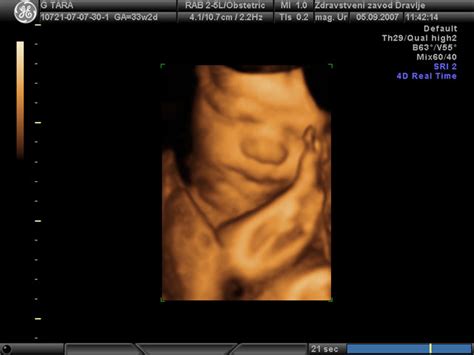

Skeletogram, ki prikazuje kosti hrbtenice, reber, nadlahtnice, podlahtnice in kosti prstov, omogoča zelo zanesljivo merjenje dolžin posameznih kosti. Vaginalni ultrazvok je v 15. tednu nosečnosti še vedno učinkovit, saj omogoča boljšo kakovost slike struktur v maternici zaradi majhne razdalje. V tem času se lahko že podrobno preučijo različni deli telesa ploda. Med 15. in 20. tednom nosečnosti je predviden pomemben pregled, imenovan "morfologija", kjer se podrobno preverijo različni deli telesa.